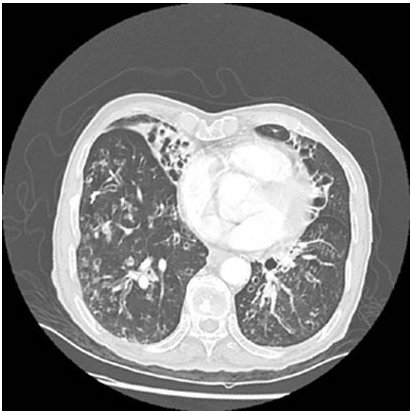

7 year hx crohns w/ 2 months of intermittent fever, nonpreoductive cough, night sweats, & fatigue. on immunotherapy. cxr showed lingular & rll infiltrates. tx with abx → no improvement. spent time in southwest usa several months ago.

coccidoides (fungus), tx w/ fluconazole